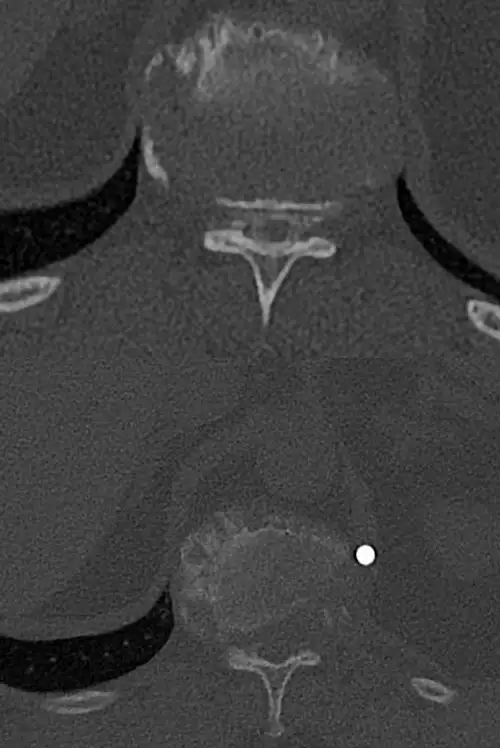

The diagnosis, in addition to being based on the symptoms and the physical examination by the specialist, is made like almost any spinal disease by means of magnetic resonance imaging (MRI), although it is usually complemented by computerized tomography (CT) and X-rays (Rx).

Sometimes contrast can be added to the intradural space in the CT and images of the spinal cord contour can be obtained (myelo-CT).